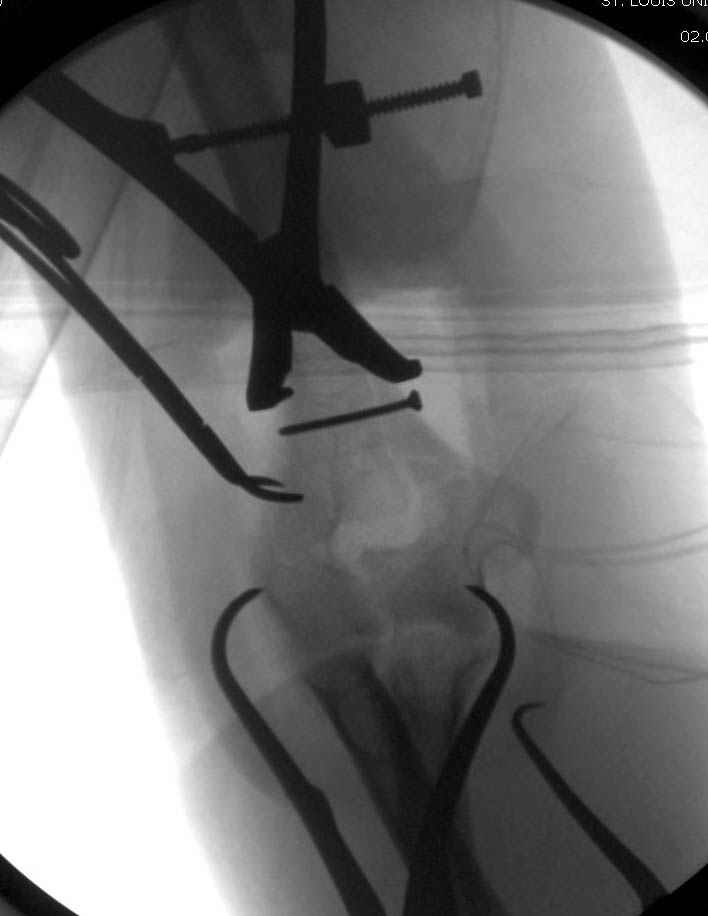

Примерный случай, только перелом был открытый, в задне-медиальной стороне рана около 2 см по характеру "изнутри кнаружи", неврологический статус со слабостью сгибания мизинца, также слабая абдукция и аддукция указательного пальца и сгибания в кисти.

Больному сделали обработку и наложили временный аппарат внешной фиксации плечо-предплечье.

На шестой день сделали открытую репозицию чрезлоктевым доступом двумя locking plate, локтевой нерв был ушибленным, после операции положительная динамика в Flexor Carpi Ulnaris. Фиксацию локтевого отростка произвели tension band technique с дополнительным шурупом.

Этапы операции на снимках....